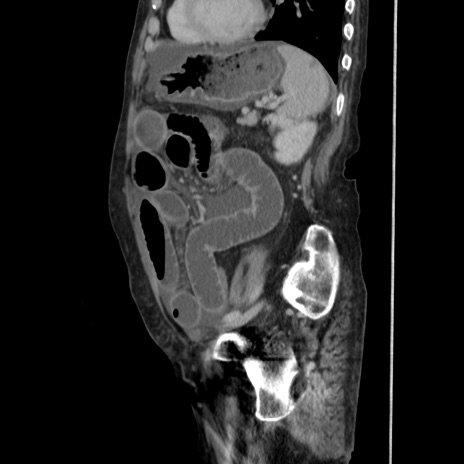

症例31(矢状断像)

【症例】80歳代 女性

【主訴】腹部膨満感

【現病歴】他院にて肝硬変にてフォロー中。1週間前から便秘、腹部膨満感、臍部腫瘤あり受診となる。

【既往歴】肝硬変

【身体所見】腹部膨隆あり、皮膚変化なし、疼痛なし。

【データ】WBC 4600、CRP 0.25